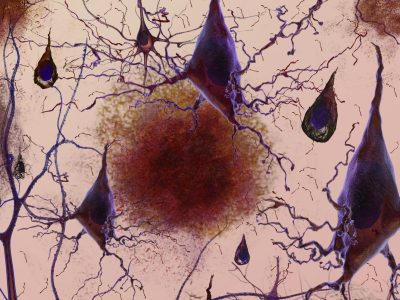

Genética de la ELA: implicaciones clínicas y avances terapéuticos

- junio 12, 2025